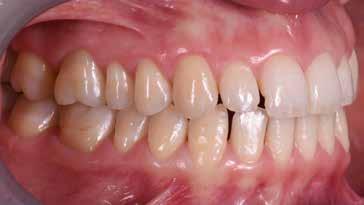

Presentazione del caso > F.V, bambino di cinque anni, presenta una malocclusione di II Classe scheletrica, III Classe dentale molare e canina destra e sinistra, morso inverso anteriore. Le arcate dentali mostrano usura degli elementi dentari anteriori a causa dell’occlusione patologica. Le linee mediane, superiore ed inferiore, sono centrate; il frenulo labiale superiore patologico per un’eccessiva estensione inter-incisale.

Una volta ottenuta la correzione del rapporto molare ed incisale, l’apparecchio elastodontico verrà portato dal paziente solo durante la notte per stabilizzare il risultato ottenuto e guidare l’eruzione degli elementi dentari per un totale di quattordici mesi di terapia. ad inizio trattamento :

Considerazioni > L’analisi cefalometrica ad inizio trattamento dimostra la II Classe scheletrica con protrusione del mascellare superiore e prognazia mandibolare; tendenza alla crescita verticale. L’esame clinico evidenzia una protrusione mandibolare funzionale.

55 54 ESTETICA FUNZIONE POSTURA Valori cefalometrici ad 1 anno di terapia : ANB ANB 3,8 Posizione del Mascellare SNA 91.40 Posizione della Mandibola SNB 87,60 Angolo Articolare SArGo 155,00 Angolo Goniaco ArGoMe 122,00 Angolo incisivo inf^Corpo madibolare IiMand 80,20 Angolo incisivo Sup^Base Cranica Ant. IsCran 111,05 Angolo Interincisivo II 138,00 72, 73 _ Over-bite e over-jet. 74 _ Immagine laterale destra. 75 _ Immagine laterale sinistra. Considerazioni > La terapia precoce di tali malocclusioni è di primaria importanza in quanto impedisce la formazione di malocclu-